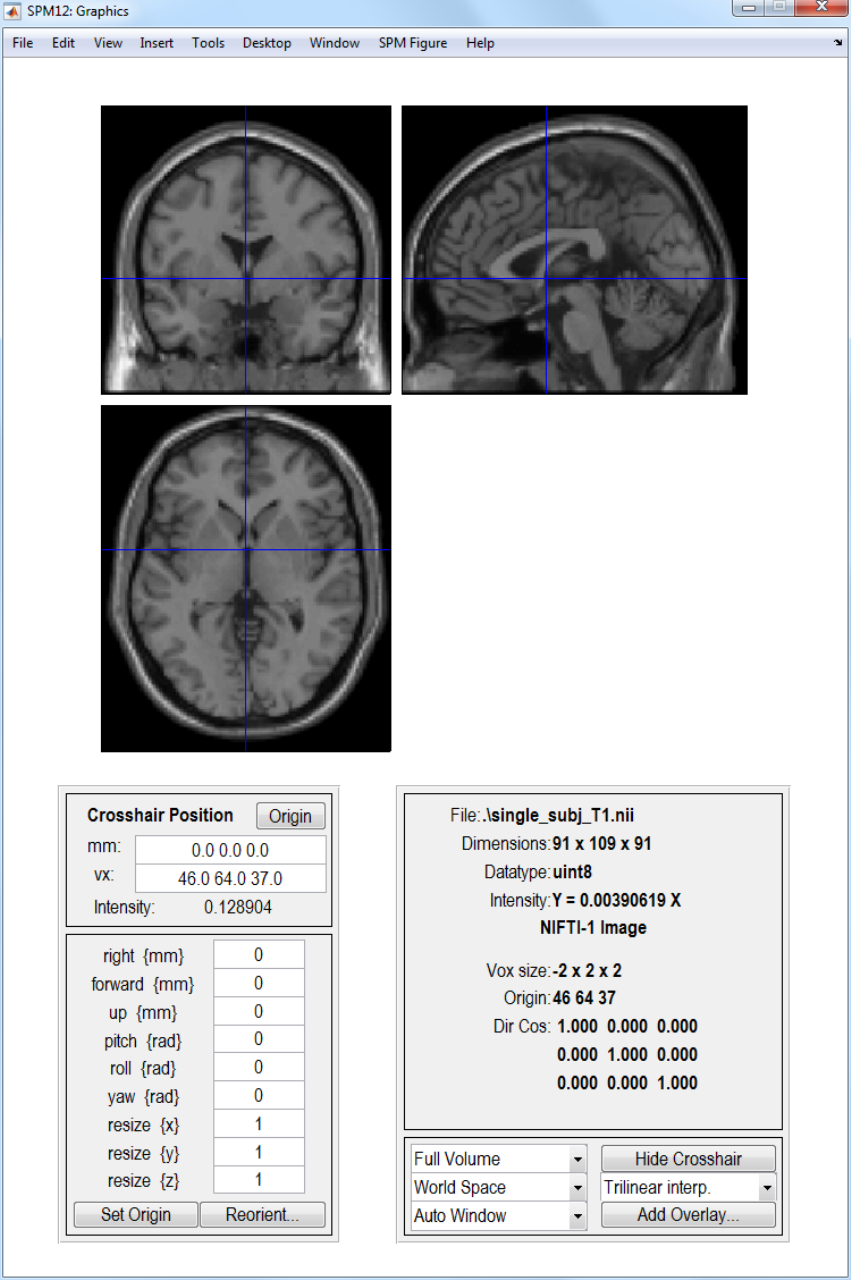

17 Display Image 145

17.1 Image to Display .....................................146